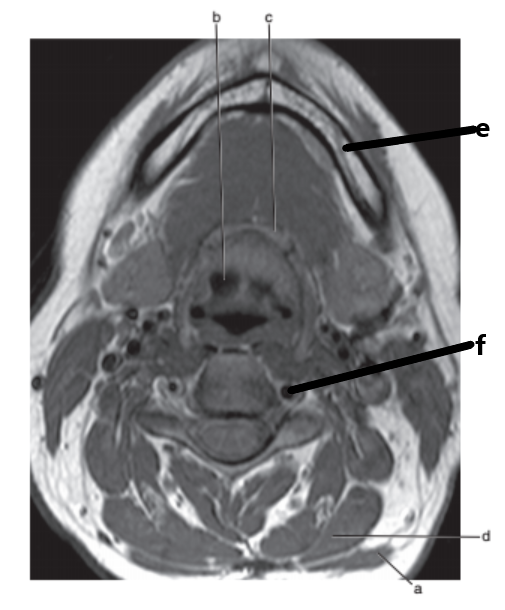

What is letter f ?

Spinal cord

Vertebral artery